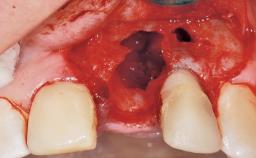

A 33-year-old female patient presented with an upper left central incisor that required extraction after a failed endodontic therapy. The tooth had been traumatized when the patient was a teenager and had undergone several endodontic treatments, including two apicectomy procedures. The patient was in good health and did not smoke. Clinical examination showed that the patient had a high lip line. In full smile, the gingival margins of the upper teeth were visible to the first molars. The gingival margins of central incisors 11 and 21 were only just showing. Examination of tooth 21 confirmed that the tooth was mobile and had hypererupted by 1 mm.

Socket Integrity Damage to one or more bone walls

Bone Volume Damage to one or more socket walls